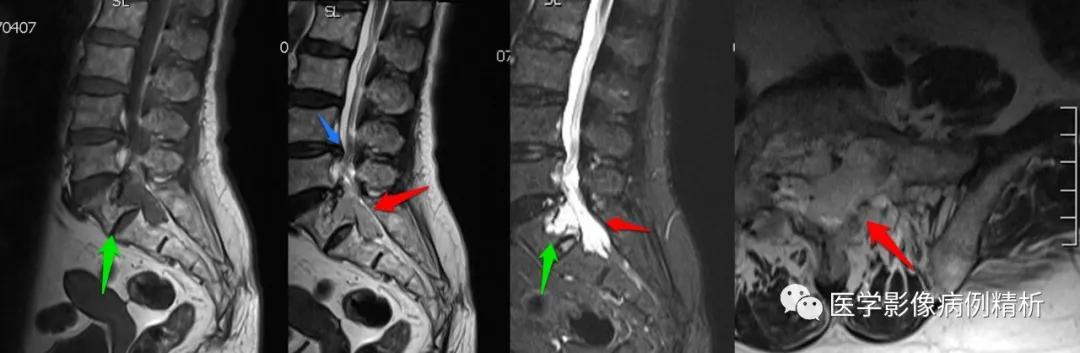

如图所示,红色箭头可见骶管及双侧骶孔扩张,内见哑铃型软组织密度影,绿色箭头所示骶骨后缘骨质受侵呈骨质破坏。

如图所示,红色箭头可见不规则形异常信号,轴位呈哑铃型,病灶前缘侵及骶1、2椎体后缘,绿色箭头见骨质局部破坏,病灶T1低信号,T2稍高信号,压脂像明显高信号,信号尚均匀,腰4-5、腰5骶1椎间盘向后方突出,硬膜囊受压,蓝色箭头可见腰4-5椎间盘后缘纤维化小点状T2高信号,提示纤维环后缘撕裂。本例骶1-2椎间盘形成,骶1椎体腰化不完全。

红色箭头:病灶位于骶1-2椎体水平,轴位呈哑铃型,CT见骶1-2椎体后缘受侵、骨质破坏;MRI见病灶主体沿骶管及双侧骶孔生长,以左侧骶孔为著,T1低信号,T2稍高信号,压脂像高信号,接近脑脊液信号。

绿色箭头:骶1-2椎体后缘见信号向内部侵犯,边缘毛糙。

绿色箭头:腰4-5、腰5骶1椎间盘向后方突出,硬膜囊受压,蓝色箭头可见腰4-5椎间盘后缘纤维化小点状T2高信号,提示纤维环后缘撕裂,需警惕未来椎间盘脱出可能。